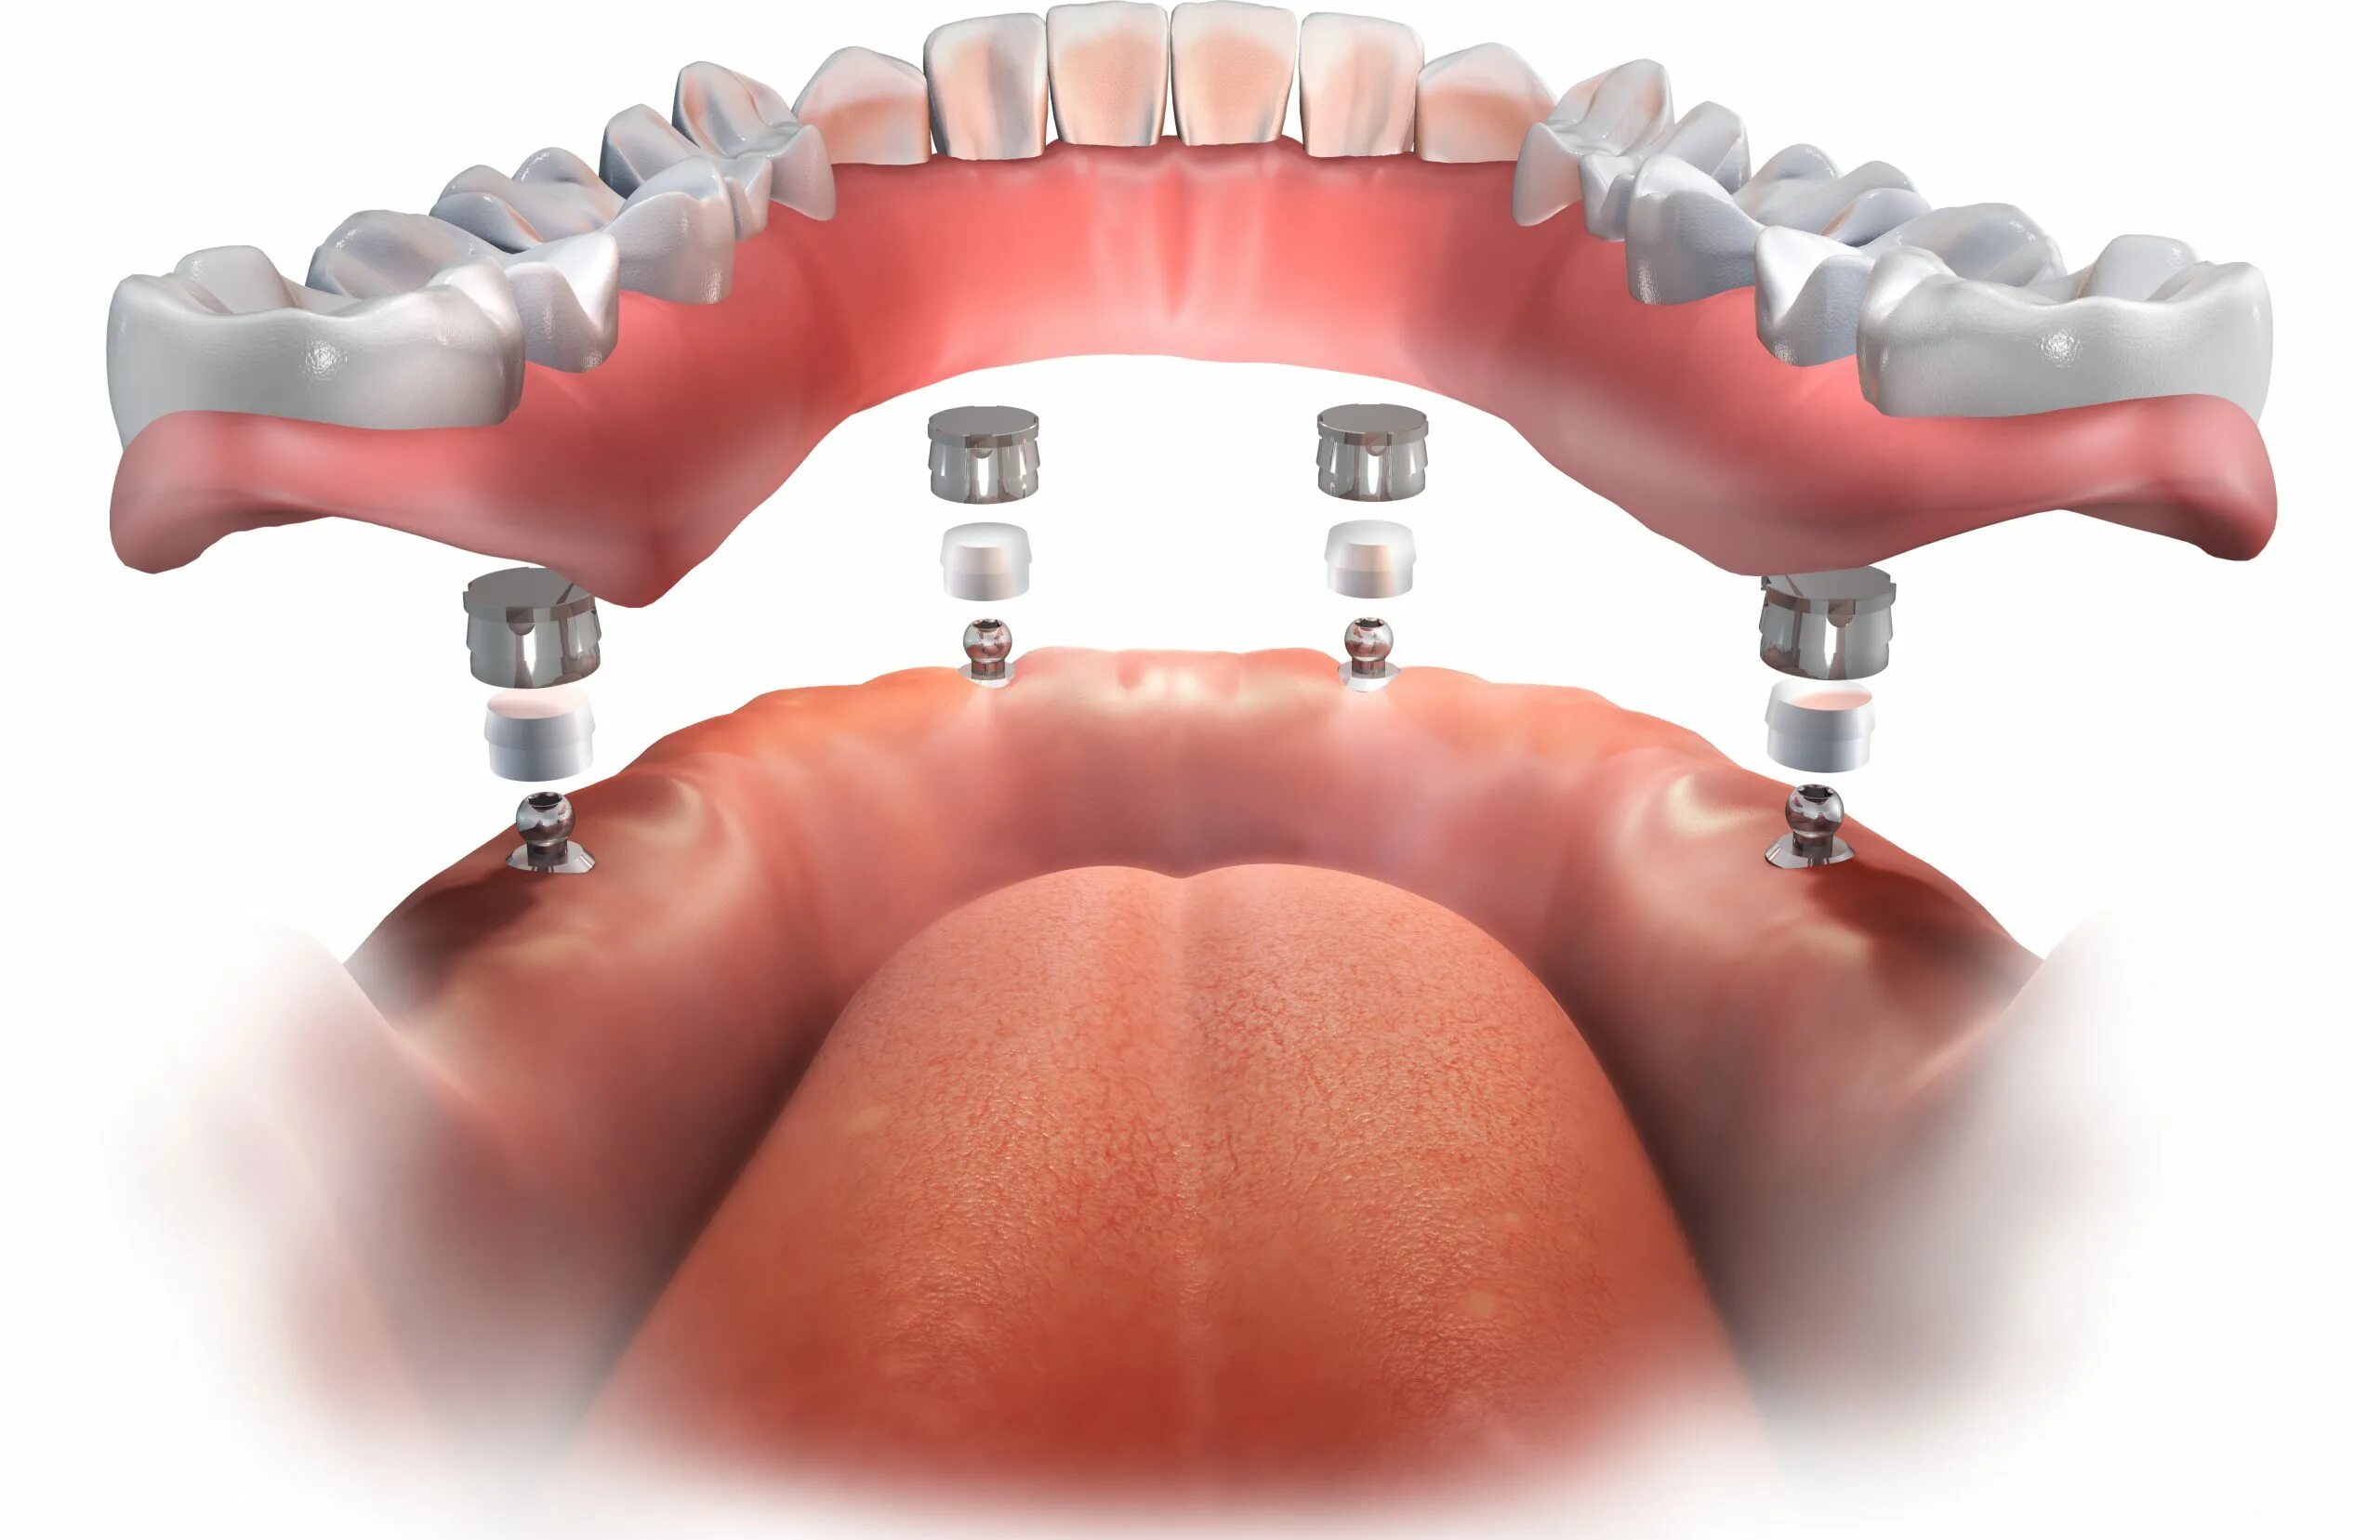

Ол он 4